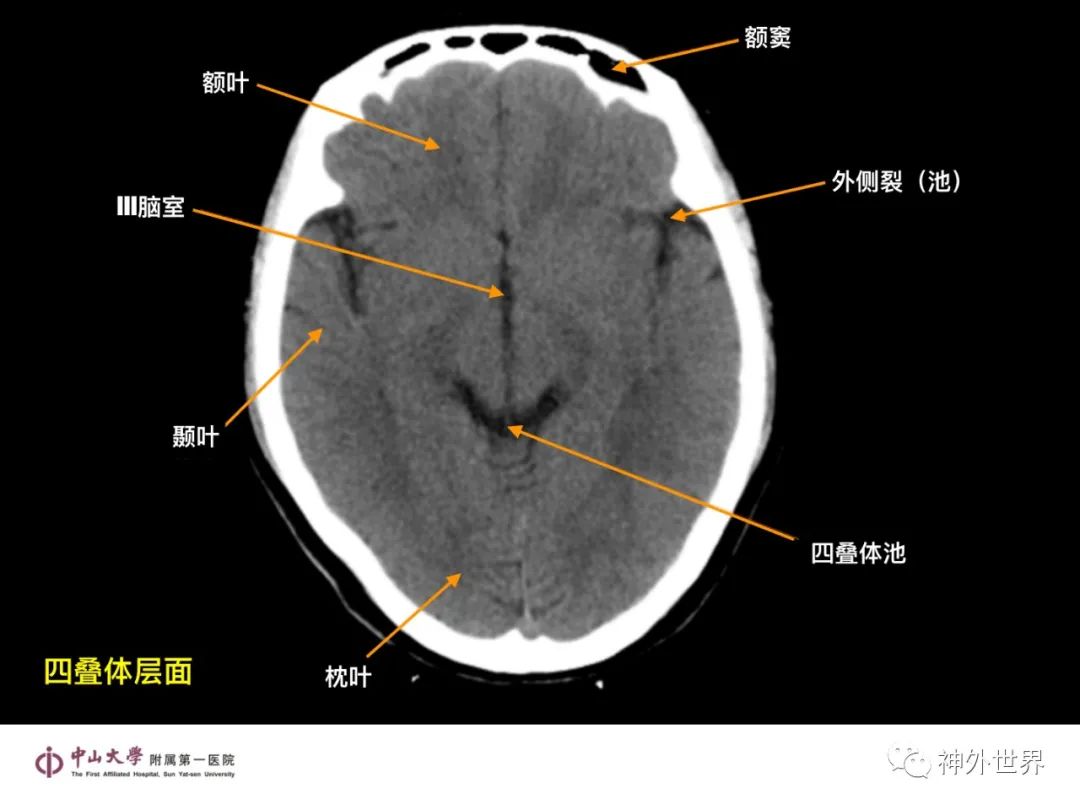

大脑MR、CT 的阅片技巧,超赞 !